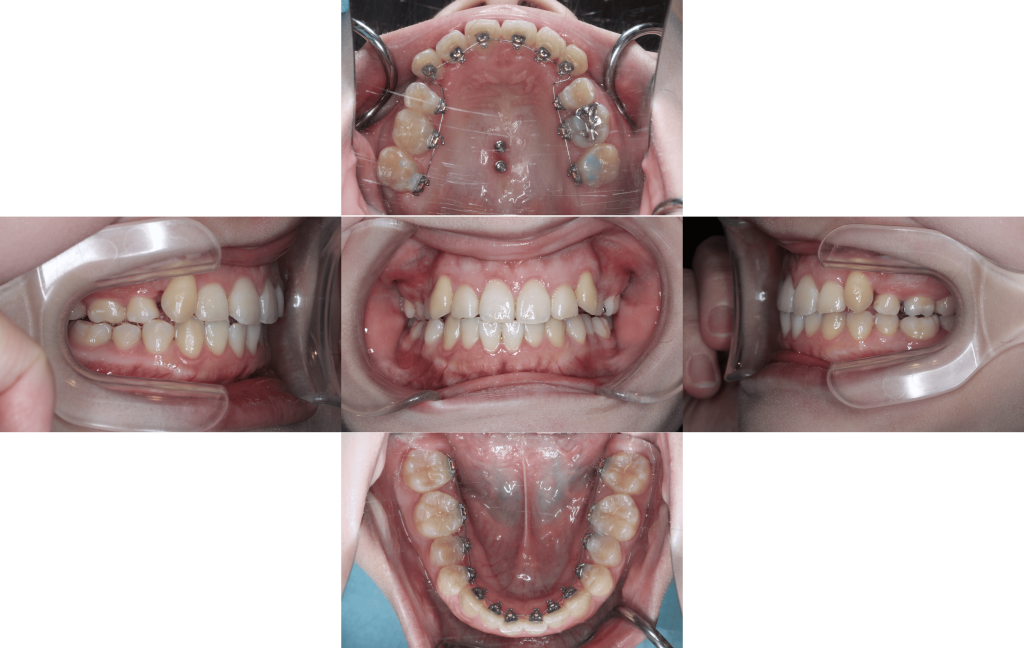

約3か月経過